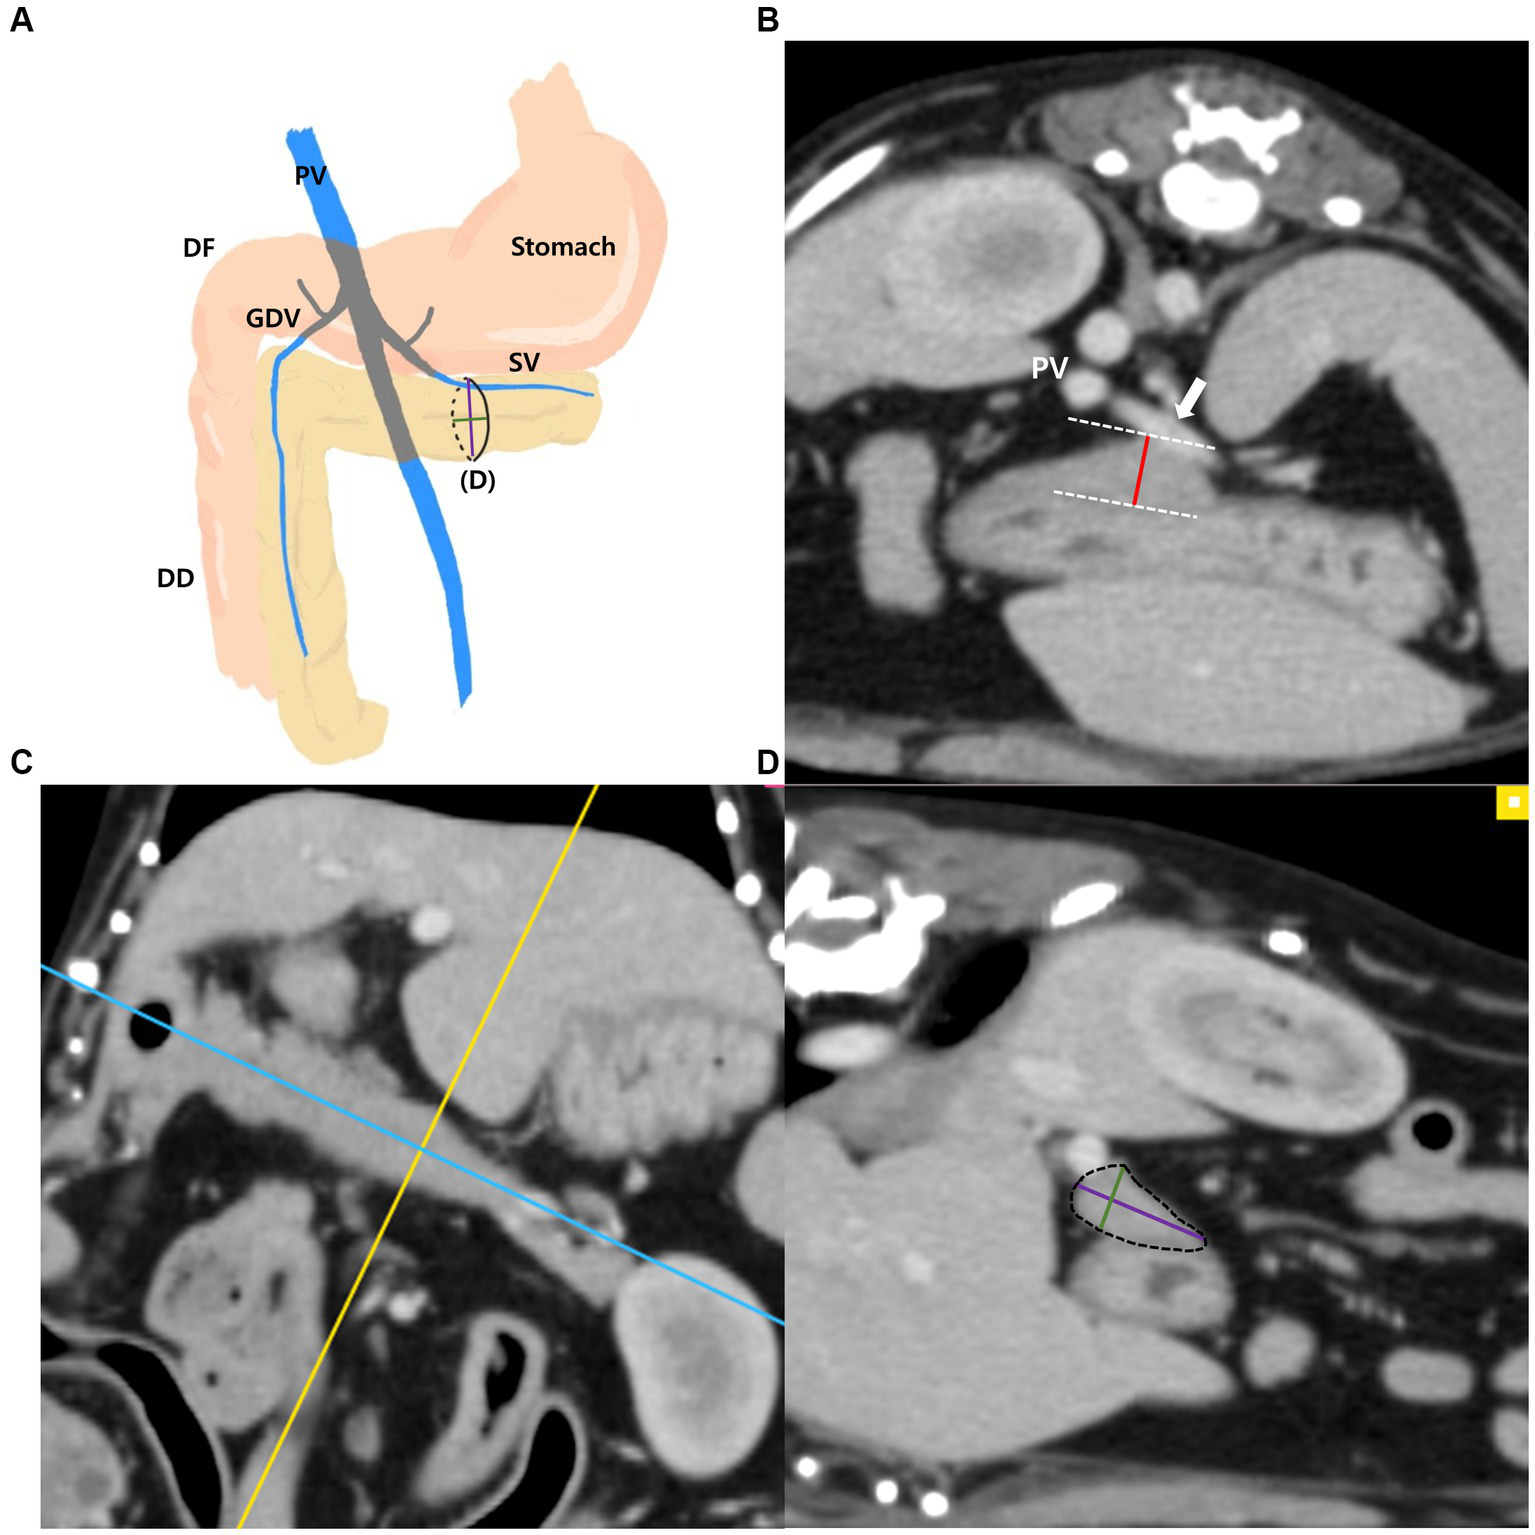

The measurements of the left pancreatic lobe (Figures 2A–D) were taken as follows: the left lobe was measured at the thickest location along the length of the left lobe extending adjacent to the splenic vein on the transverse plane (Figure 2B). Additionally, in the thickest part, MPR was performed perpendicular to the long axis of the left lobe on the dorsal plane (Figure 2C). The long axis of the pancreas was set to be parallel to the pancreas and through the middle. In the cross-sectional image (oblique sagittal MPR plane) of the long axis of the left lobe, two dimensions perpendicular to each other were measured (Figure 2D). Two dimensions were measured at the longest location and the shorter dimension was called the “short dimension” and the longer dimension was called the “long dimension,” respectively (Figure 2D).

Figure 2

Measurements of the left pancreatic lobe. Schematic illustration of pancreas (A), transverse plane (B), dorsal plane (C) and oblique sagittal MPR plane (D). The thickness of the left lobe was measured at the thickest location along the length of the left lobe (white arrow, splenic vein) (B). On the dorsal plane (C), long axis (blue line) of pancreas was set to be parallel to the pancreas and through the middle. MPR was performed perpendicular (yellow line) to the long axis (blue line) of the left lobe at the thickest part. In the oblique sagittal MPR plane (D) which is cross sectional image at the yellow line, short and long dimensions perpendicular to each other were measured at their longest length (Green, short dimension; Purple, long dimension). PV, portal vein; DF, duodenal flexure; DD, descending duodenum; GDV, gastroduodenal vein; SV, splenic vein (white arrow).

The measurements of the right pancreatic lobe were taken as follows (Figures 3A–D): the right lobe was measured at the thickest location in the region that runs along the descending duodenum on the transverse plane (Figure 3B). Additionally, in the thickest part, MPR was performed perpendicular to the long axis of the right lobe on the dorsal plane (Figure 3C). The long axis of the pancreas was set to be parallel to the pancreas and through the middle. In the cross-sectional image (oblique transverse MPR plane) of the long axis of the right lobe, two dimensions perpendicular to each other were measured (Figure 3D). Two dimensions were measured at the longest location and the shorter dimension was called the “short dimension,” and the longer dimension was called the “long dimension,” respectively (Figure 3D).

Figure 3

Measurements of the right pancreatic lobe. Schematic illustration of pancreas (A), transverse plane (B), dorsal plane (C) and oblique transverse MPR plane (D). The thickness of the right lobe was measured at the thickest location in the region that runs along the descending duodenum (DD) (B). On the dorsal plane (C), long axis (yellow line) of pancreas was set to be parallel to the pancreas and through the middle. MPR was performed perpendicular (blue line) to the long axis (yellow line) of the right lobe at the thickest part. In the oblique transverse MPR plane (D) which is cross sectional image at the blue line, short and long dimensions perpendicular to each other were measured at their longest length (Green, short dimension; Purple, long dimension). PV, portal vein; DF, duodenal flexure; DD, descending duodenum; GDV, gastroduodenal vein; SV, splenic vein; RK, right kidney.